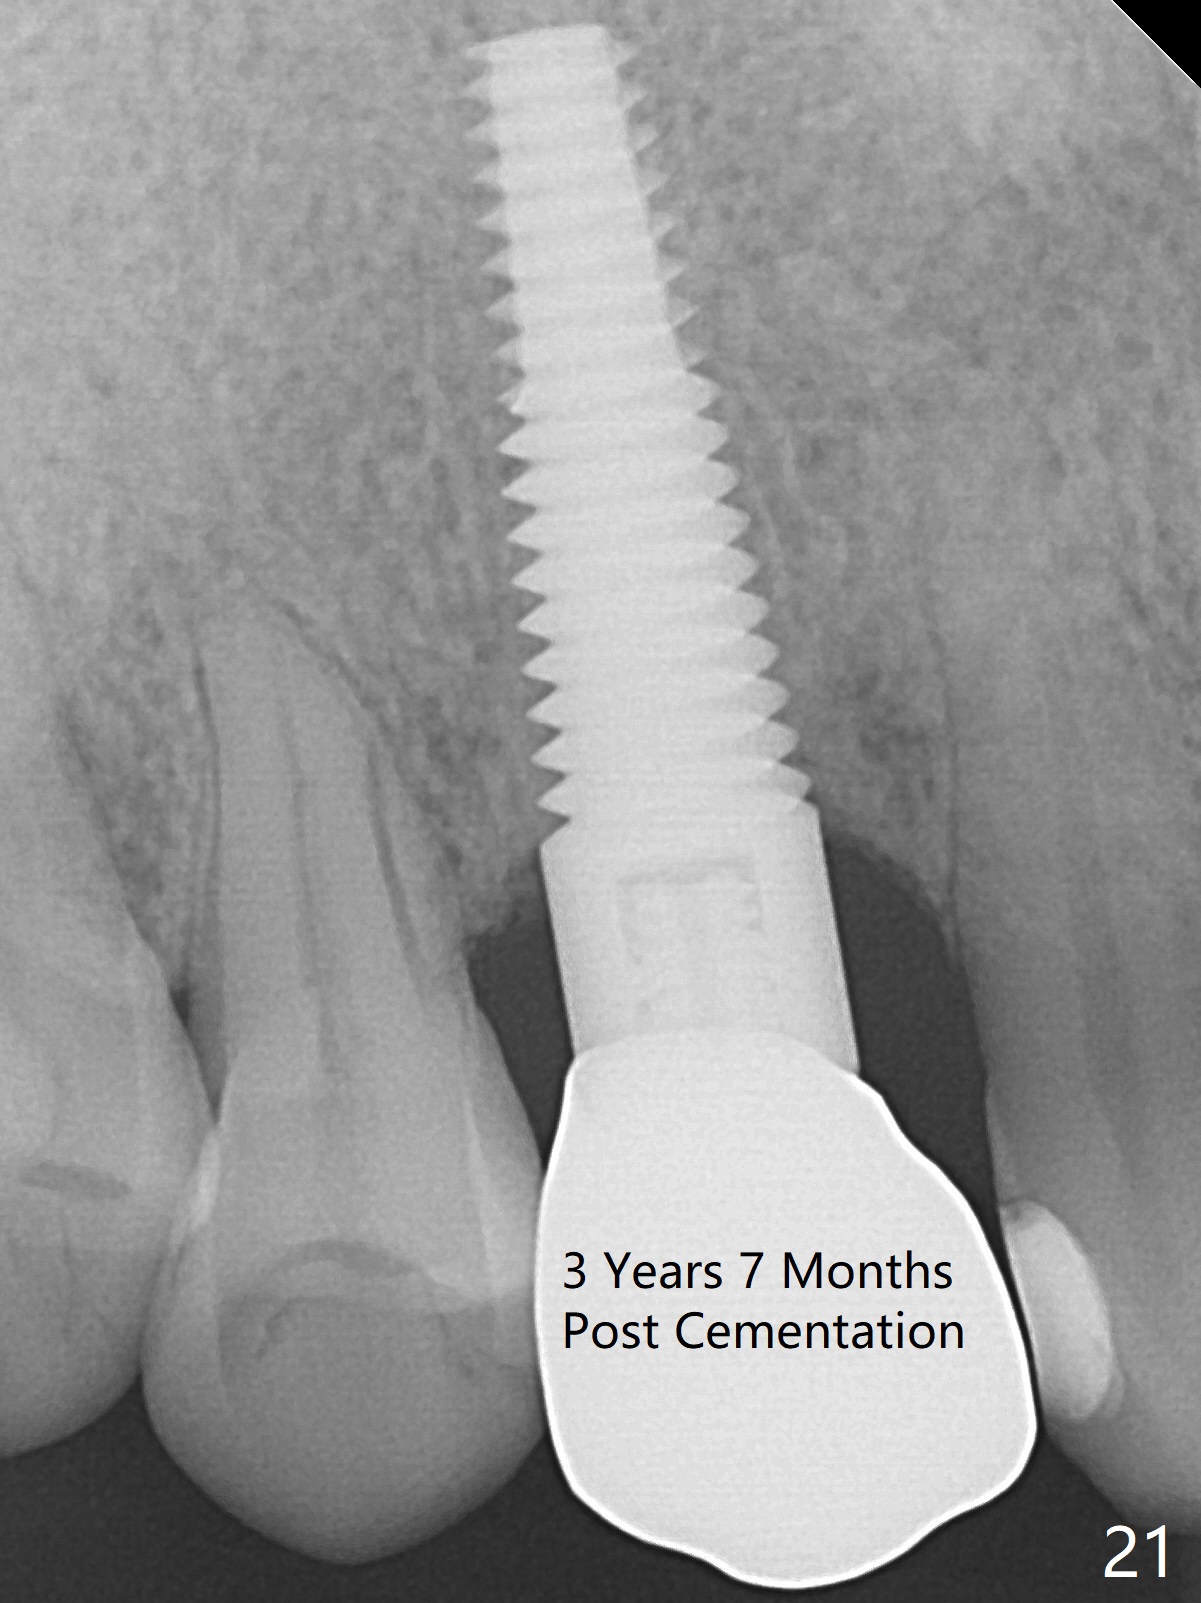

To be improved: 1. Implant could be placed more palatal; 2. Gingival laceration should have been sutured prior to bone grafting; 3. The buccal margin of the provisional should have been extended more buccally to prevent bone graft from dislodgement; the provisional should be relined and recemented securely; 4. More rigid membrane should have been used to keep convexity of the buccal plate. The crestal bone is stable 3 Years 7 Months Post Cementation (Fig.21). The buccal plate is slightly atrophic 3 Years 7 Months Post Cementation (Fig.22).